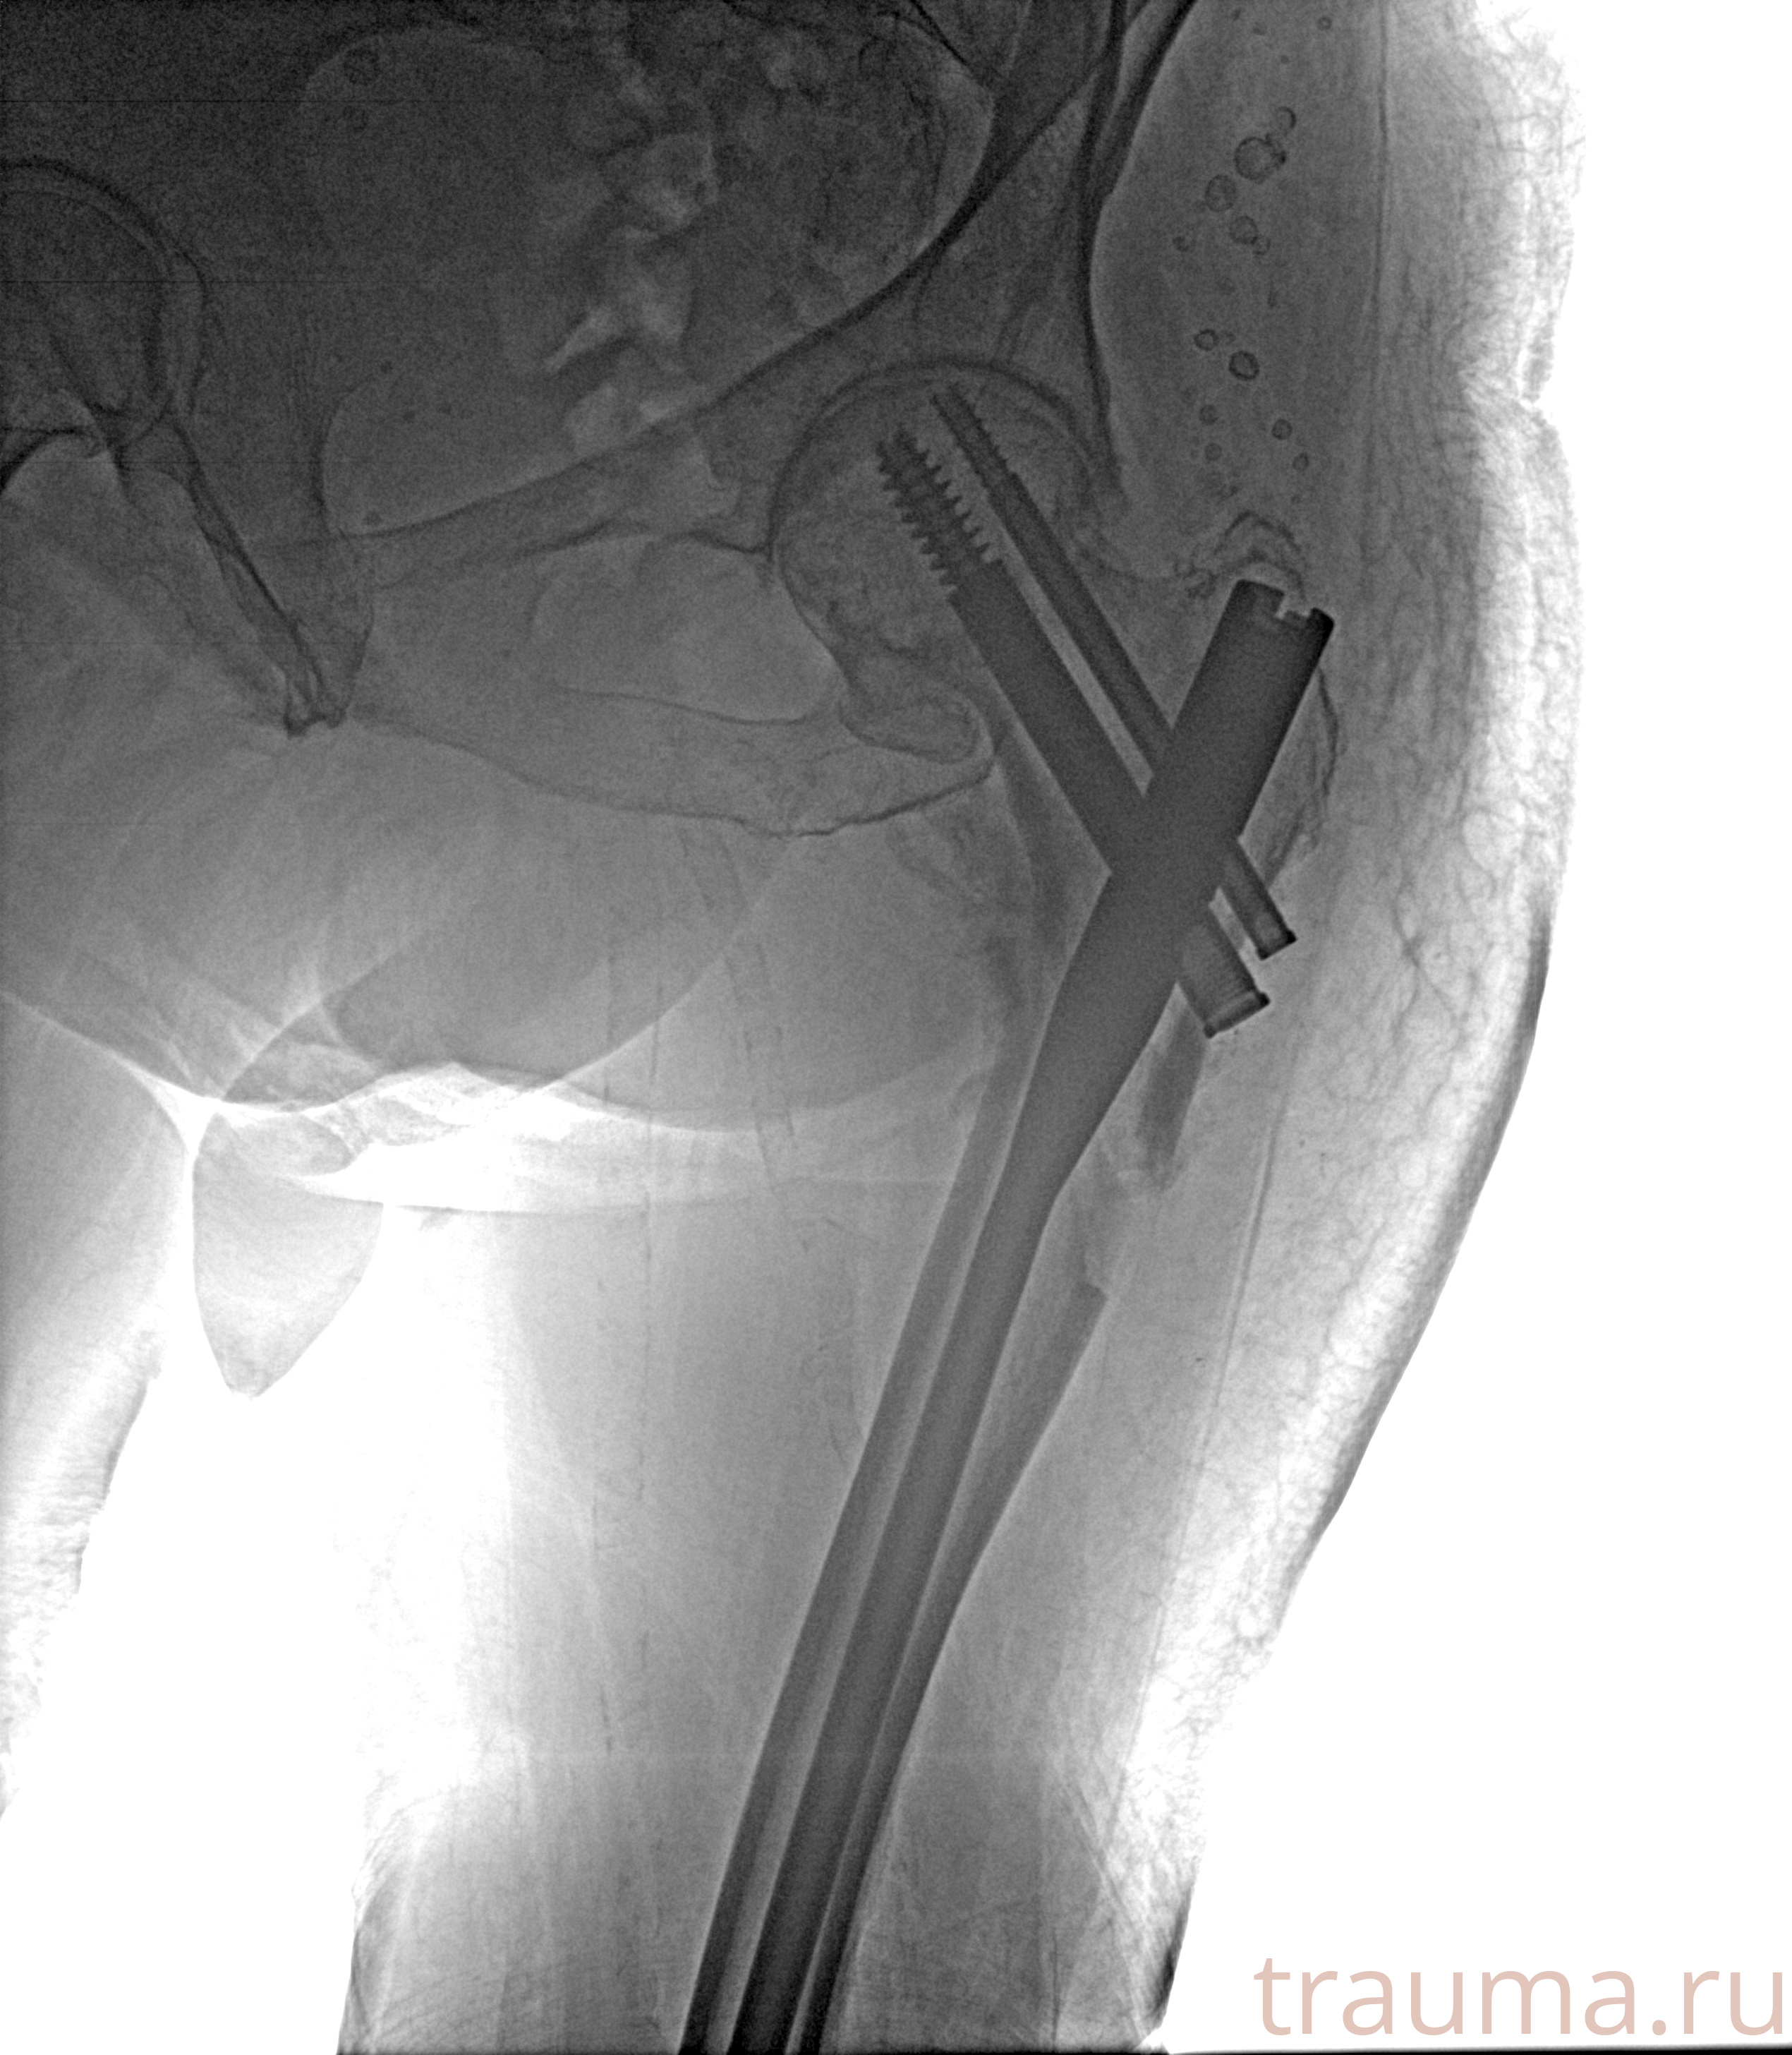

Рентгенограммы

Рентген на дому: по вашему адресу приезжает врач-рентгенолог, травматолог-ортопед с мобильным рентгеновским аппаратом, проводит диагностику травмы или заболевания, делает необходимые рентгенограммы, дает рекомендации по дальнейшему лечению. Получить качественные снимки в домашних условиях возможно благодаря уникальной методике, разработанной МосРентген Центром для института  Склифосовского